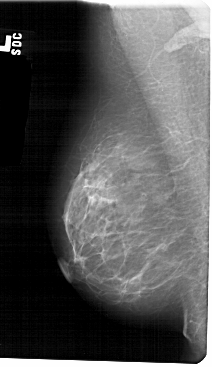

A_1310_1.LEFT_MLO

LEFT_MLO LINES 5491 PIXELS_PER_LINE 3166 BITS_PER_PIXEL 12 RESOLUTION 43.5 NON_OVERLAY